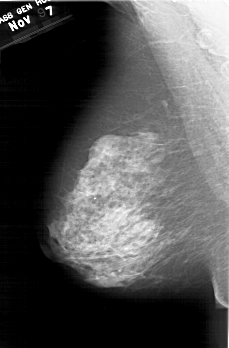

A_1416_1.LEFT_MLO

LEFT_MLO LINES 6601 PIXELS_PER_LINE 4336 BITS_PER_PIXEL 12 RESOLUTION 43.5 NON_OVERLAY